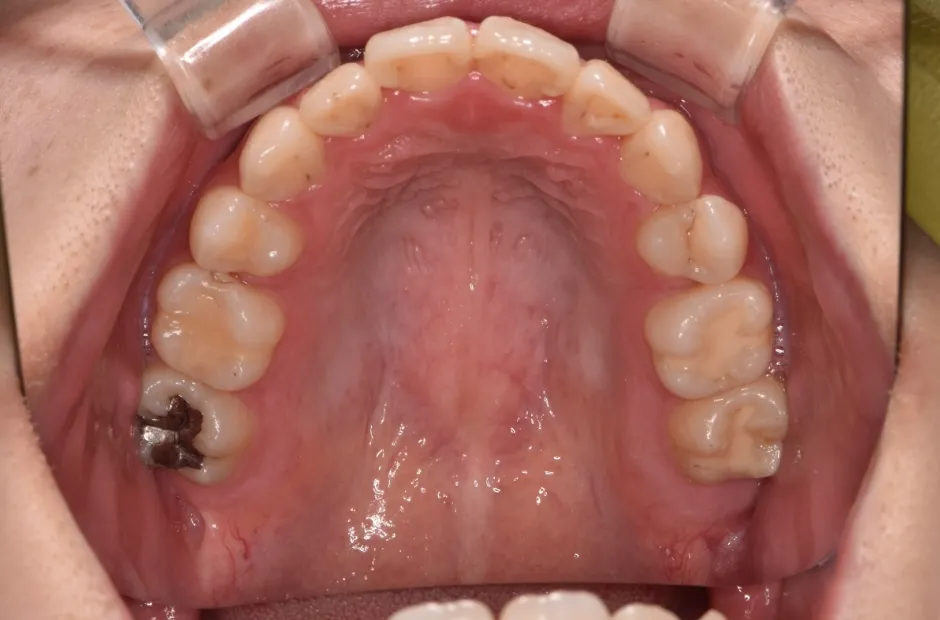

叢生

| 診断名・主訴 | 叢生 |

|---|---|

| 年齢・性別 | 43歳・女性 |

| 治療期間・回数 | 2年7か月 27回 |

| 治療に用いた主な装置 | 舌側矯正 |

| 抜歯部位 | 両顎4,4 |

| 治療費 | 100万円(税抜) |

| リスク・副作用 | 装置による違和感・疼痛・歯肉退縮・歯根吸収・虫歯のリスクなど |

治療前